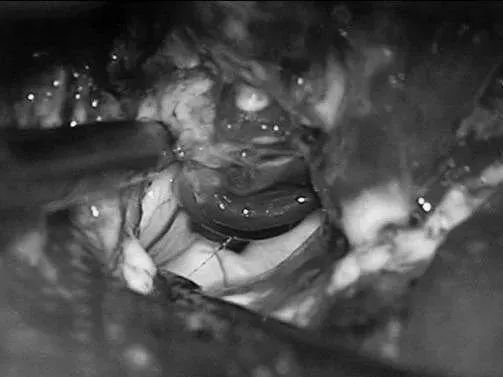

Lawton教授术中操作

左侧翼点开颅,再次手术,显露前颞叶。

沿颞下回经原皮层入路达颞角。

AChA经脉络裂进入颞角,在前方供应AVM,lPChA在后方供应AVM。

通过ITG经皮层显露可以充分显露颞角,达到全切AVM。